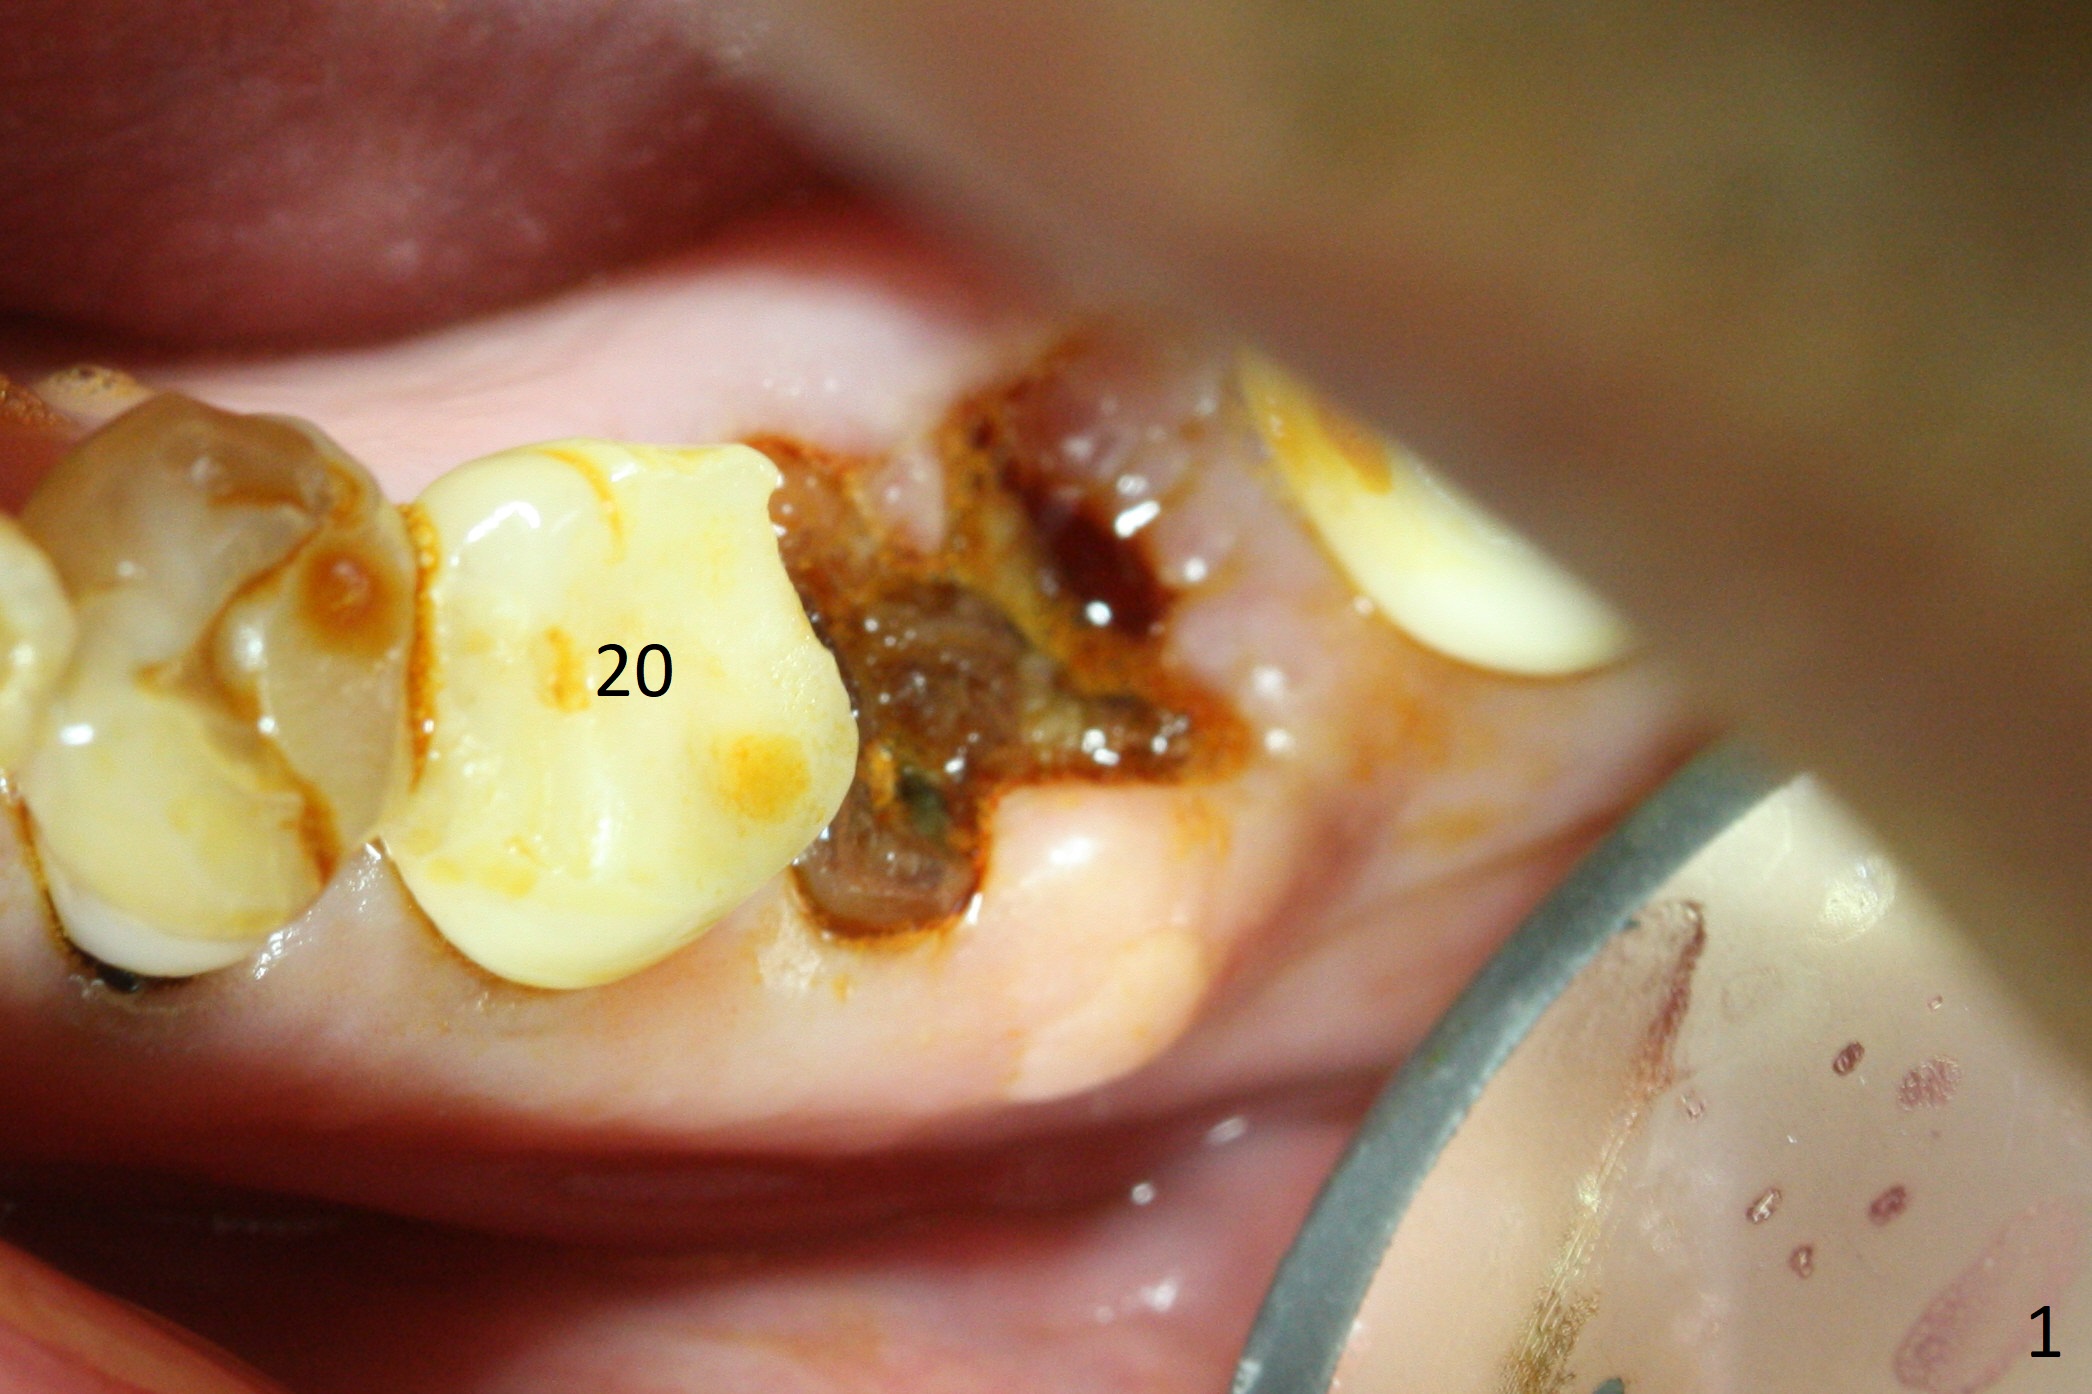

Extraction of the residual roots at #19 (Fig.1) is difficult, partially due to the hard one. The latter contributes to primary stability of 5x10 mm IS implant placed in the septum (Fig.2 (*),3). After change of cementation abutment (5.2x4.5(2) mm (short for provisional)) to hexed temporary abutment (5.2x8(2) mm), Collagen plug and Vera Graft are placed in the remaining mesial and distal socket (Fig.4 *). The last PA is taken when the temporary abutment (Fig.6 (<: hexed portion)) and provisional (P) are removed for modification. Before the abutment/provisional complex returns, a 2nd round of graft is placed (Fig.5 *). After the complex is seated, a 3rd round of graft is placed buccally (Fig.7). The temporary abutment is retightened 2 months postop (Fig.8). The implant appears to be osteointegrated 3.5 months postop (Fig.9). The gingiva looks healthy with (Fig.10) and without the provisional (Fig.11,12). It appears that there is no or minimal buccal plate loss. After insertion of a 5.7 x3 mm 15 degree (B-type) angled abutment (Fig.13) and height adjustment, impression is taken. The provisional is reseated after impression. The mesial bony defect seems to have been repaired nearly 8 months postop, 3 months post cementation (Fig.14 *). The bone density increases mesially 11 months post cementation (Fig.15).